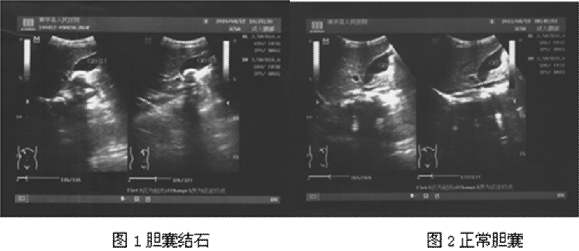

典型胆囊结石超声图像特点:(1)胆囊形态清晰

579x251 - 102KB - PNG